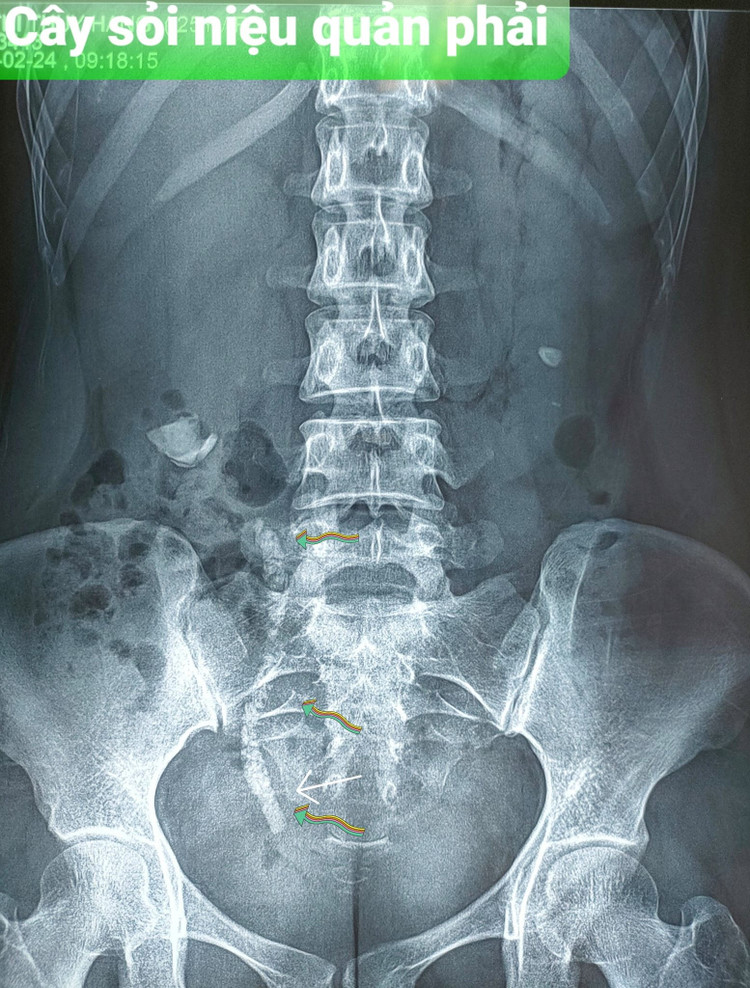

Bệnh nhân N.T.P. (Nam Định) có sỏi thận 2 bên, đã tán sỏi ngoài cơ thể. Bệnh nhân được khẳng định là hết sạch sỏi sau tán sỏi qua da... nên chủ quan. Sau 2 năm bệnh nhân đi khám thì sỏi đã xếp thành chuỗi ở niệu quản > 20cm và thận đã ứ nước rồi...

soi-nieu-quan-1.jpg